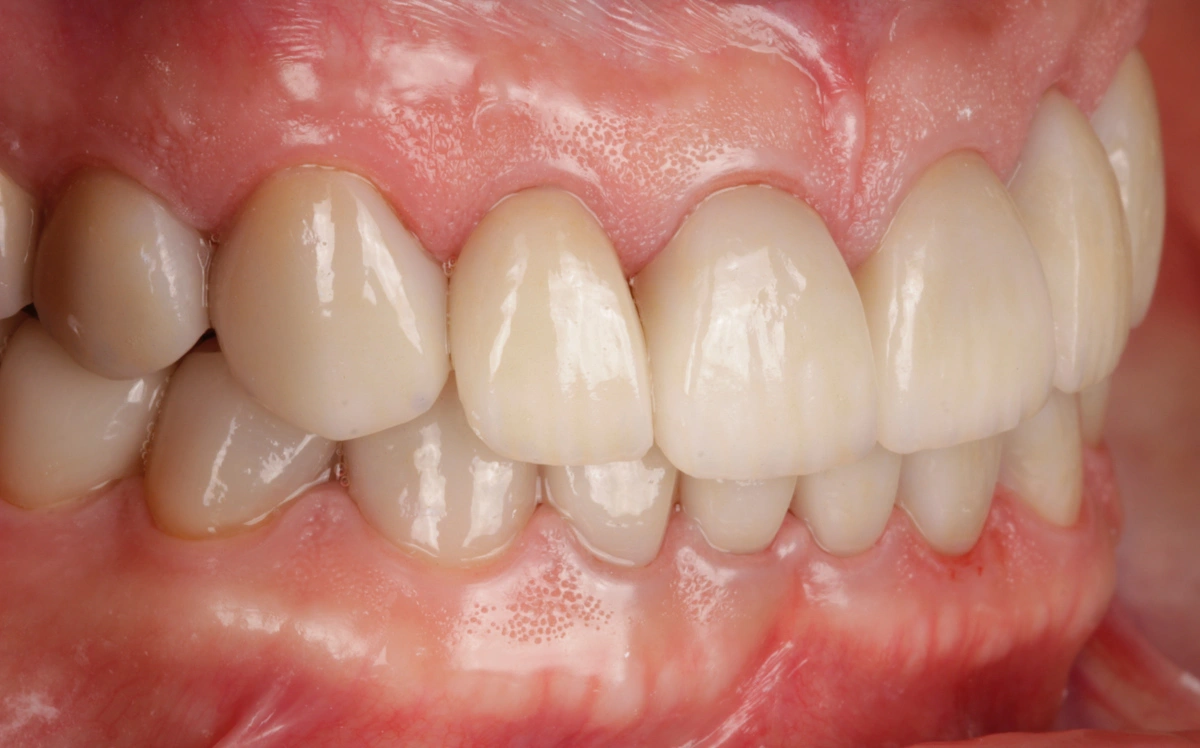

«Rehabilitación completa adhesiva en paciente joven con desgaste dental severo y tinción por tetraciclinas.»

En este caso se trata de un paciente con desgaste dental severo y tinción por tetraciclinas grado IV.

Tras realizar un estudio exhaustivo optamos por una rehabilitación completa con coronas, carillas e incrustaciones en disilicato de litio. Realizamos una prueba previa a la preparación de los dientes para establecer la longitud de los dientes definitivos.